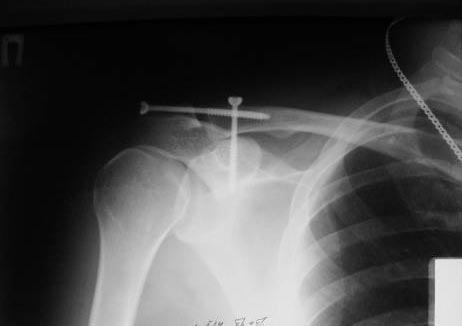

[Ortho] фиксация КАС по Веберу

А зачем фиксировать по Веберу, если можно двумя винтами чрезкожно.

В начале использовали канюлированные, а затем обычные (канюлированные

жалко). Фото в приложении. Операция под ЭОПом.

Травма свежая.